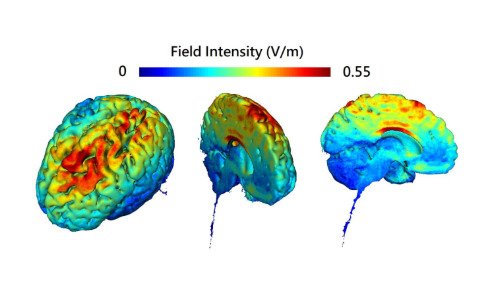

Tecnología Fractal de Activación Prefrontal

Despierta tu Súpercerebro

HybridWave™ amplifica la activación del Neocórtex.

Gracias a su tercera capa de tecnología-fractal de activación prefrontal.

Amplifica la neuroplasticidad, mejorando la capacidad de aprender y adaptarse en tiempo real.

Conviertiendo el proceso de aprendizaje en superaprendizaje, emulando a Einstein.